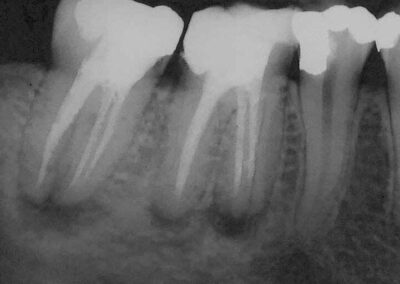

Verlaufskontrolle im November 2002 ohne röntgenologisch knochendichte Ausheilung der Resektionshöhlen (Klick!)